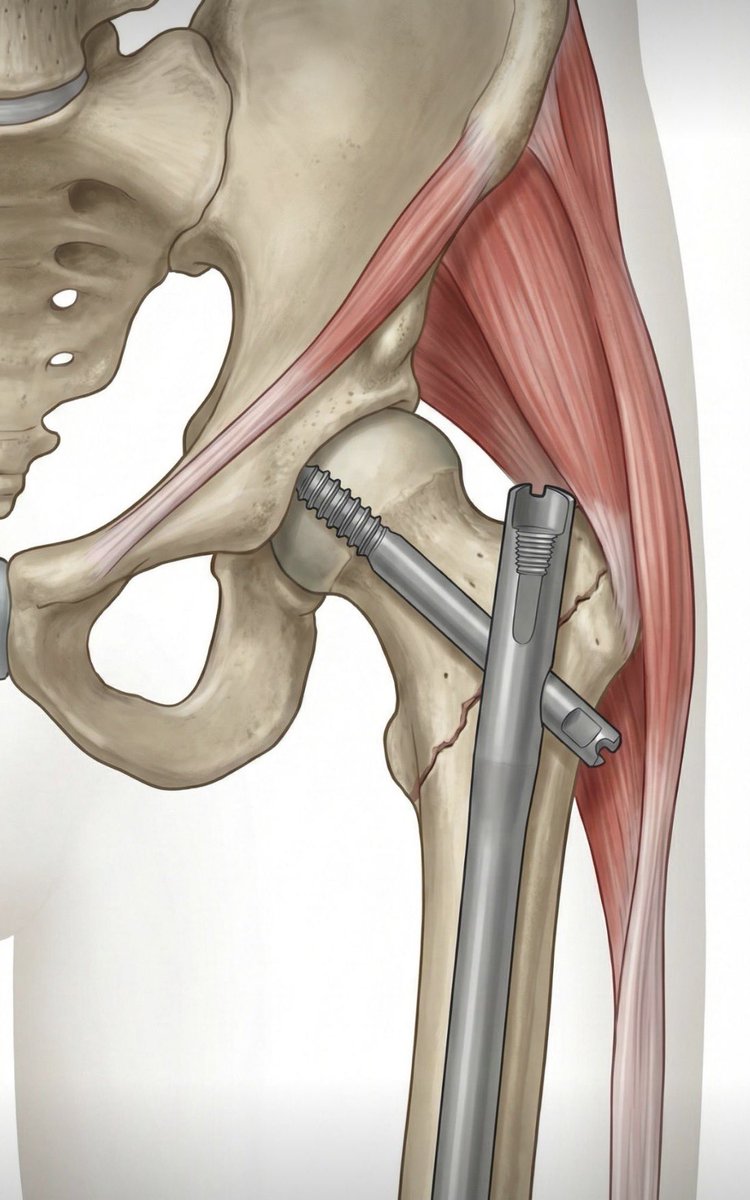

Neck of femur fracture in 55 year old gentleman,

Pauwel type 2

Mild Comminuted !

Did DHS with CC Screw.

#medtwitter #medx #orthotwitter #orthox #fracture

@pratikorho good construct for such a pattern. Without knowing patient factors, THR is not for everyone and has a distinct complication spectrum

the TAD is for IT fractures. using 2 points of fixation controls rotation while providing fixed angle support.

which one is placed first?